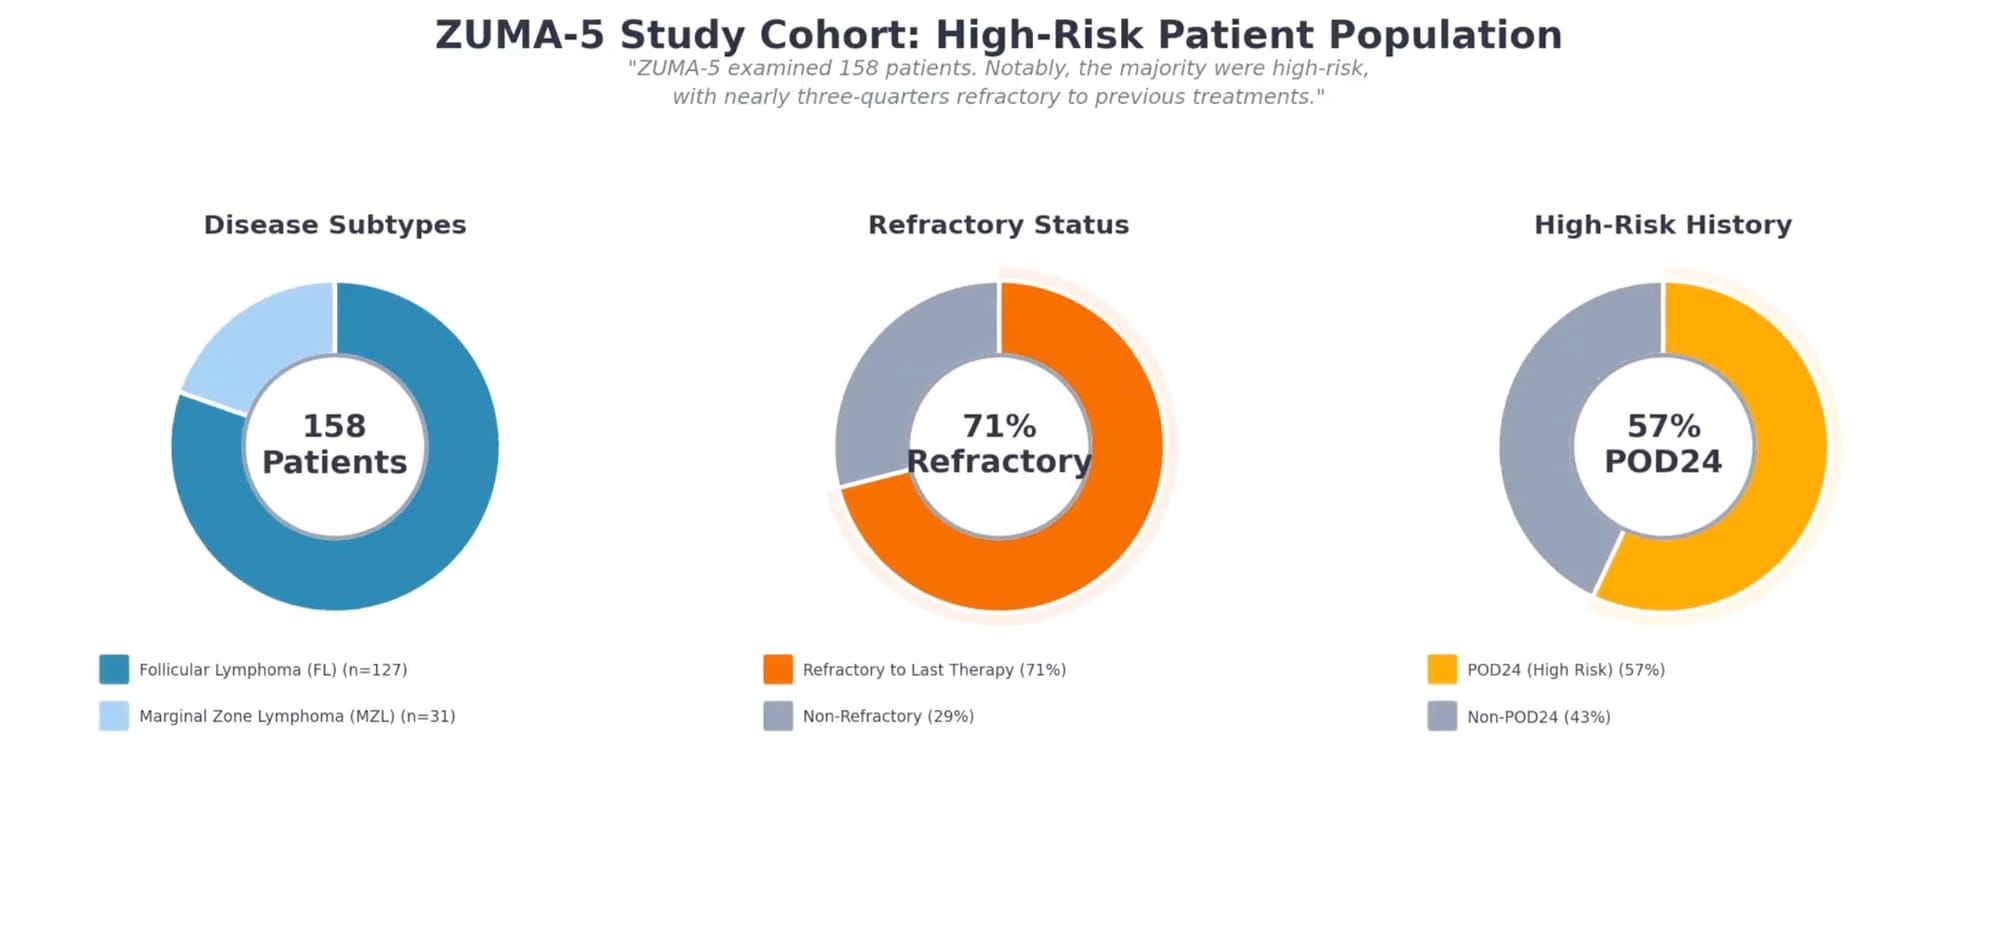

Study Design and Patient Population

ZUMA-5 enrolled 159 patients with relapsed or refractory indolent non-Hodgkin lymphoma, including 127 with follicular lymphoma and 31 with marginal zone lymphoma. This was a heavily pretreated population: patients had received a median of three prior therapies, 64% had received three or more prior lines, and 71% were refractory to their most recent treatment.

Notably, 57% of patients had experienced POD24—early progression after initial anti-CD20 therapy—a characteristic associated with inferior outcomes. More than half had high tumor bulk by GELF criteria, and 87% had advanced-stage disease. This patient population represents those with the greatest unmet need: individuals for whom standard options had already failed.

Of the 159 enrolled patients, 152 received axi-cel infusion at a target dose of 2 × 10⁶ CAR T cells/kg following fludarabine and cyclophosphamide conditioning.